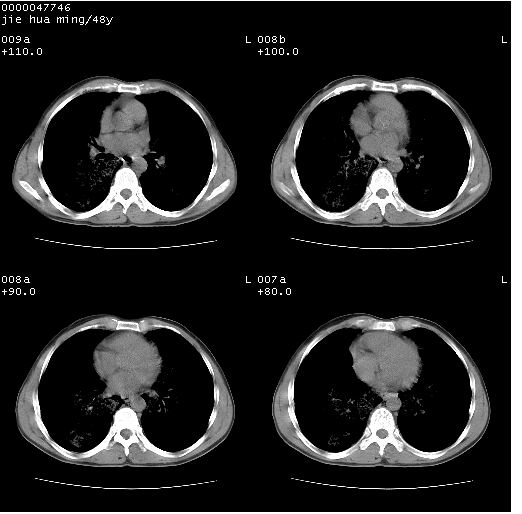

以下是引用dr.yang在2008-5-1 6:25:00的发言:[br]两肺广泛毛玻璃样的片状影,密度不均,边缘欠清,呈碎石路样改变,[br]考虑,1双肺间质性肺炎,2肺泡蛋白沉积症3支气管肺泡癌[br]

以下是引用hhcckk在2008-5-1 8:06:00的发言:[br]支持肺泡蛋白沉积症[br]依据:[br]1、病灶边缘清楚----地图征[br]2、病灶内部小叶间隔或小叶内间隔增厚所形成的网格状影----碎石路样表现[br]3、抗炎治疗无效(炎症抗炎治疗有效)[br]4、纵隔内未见肿大淋巴结(肺泡细胞癌时常有)[br][br]附肺泡蛋白沉积症资料[br][br]肺泡蛋白沉积症(pulmonary alveolar proteinosis)是一种原因不明的以肺泡腔内大量含脂糖蛋白样物质沉积为特征的疾病。[br]病理改变:(1)肺泡和细支气管腔内充满大量含脂糖蛋白样的粘稠物质,该物质为颗粒状或絮状的糖原pas染色阳性的磷脂蛋白。(2)肺泡壁及其间隔无异常改变。胸膜和淋巴结不受累及。(3)晚期可出现弥漫性肺间质纤维化。[br]临床表现:(1)好发年龄30~50岁,男性多于女性,偶见于儿童;(2)主要症状为呼吸困难、咳嗽、低热、消瘦、低氧血症和杵状指等。1/3的患者无症状。(3)实验室检查:痰液或肺泡灌洗液中可找到pas染色阳性颗粒物质。[br]hrct表现:肺泡蛋白沉积症具有特征性改变,即“碎石路样”表现(crazy-paving appearance,cpa)。主要包括(1)斑片状磨玻璃影:指肺野密度朦胧增加,内可见肺血管纹理影,系肺泡腔内充满低密度的磷脂蛋白物质所致。(2)其内部小叶间隔或小叶内间隔增厚所形成的网格状影,为小叶间隔水肿、肺泡壁内淋巴细胞和巨噬细胞浸润以及小叶内淋巴管扩张的缘故。(3)病灶边缘清楚,呈地图样分布于肺野外围或肺门及中央区。[br]

以下是引用zsl6918在2008-5-1 7:35:00的发言:[br]双肺磨玻璃样病变,可见铺碎路石征,病变区与正常区交错。边界清晰。符合肺泡蛋白质沉着征,高分辨扫描会更清楚漂亮。建议临床肺泡灌洗。

以下是引用yangyudong333在2008-5-1 5:36:00的发言:[br][br] 两肺广泛毛玻璃样的片状影,密度不均,边缘欠清,呈碎石路样改变,[br]考虑,1双肺间质性肺炎,2肺泡蛋白沉积症[br]